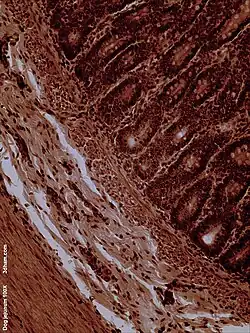

The jejunum contains very few Brunner's glands (found in the duodenum) or Peyer's patches (found in the ileum). However, there are a few jejunal lymph nodes suspended in its mesentery. The jejunum has many large circular folds in its submucosa called plicae circulares that increase the surface area for nutrient absorption. The plicae circulares are best developed in the jejunum.

Dog jejunum (magnified 100-fold)